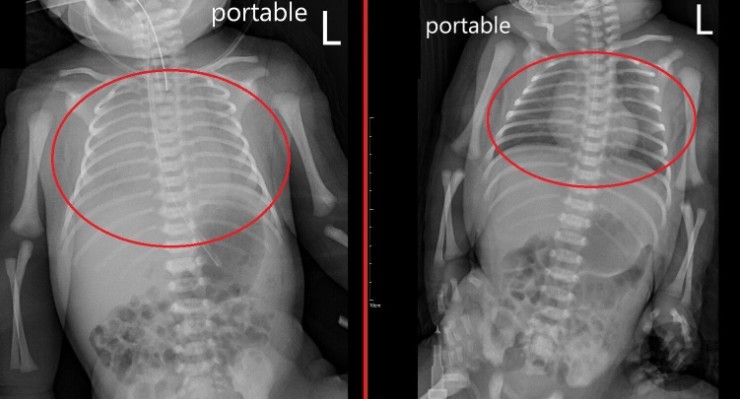

Qua thăm khám và làm các xét nghiệm cần thiết, các bác sĩ chẩn đoán bé mắc viêm phổi bẩm sinh – một trong những bệnh nhiễm trùng nguy hiểm ở trẻ sơ sinh. Theo bác sĩ Tôn Nhược Nghiêu, Trưởng khoa Nhi, bệnh có thể làm suy giảm nghiêm trọng chức năng trao đổi khí của phổi. Nếu không được can thiệp kịp thời, nguy cơ tử vong là rất cao.

Do tình trạng suy hô hấp nặng, ê-kíp điều trị đã tiến hành đặt nội khí quản, sử dụng máy thở để duy trì oxy cho cơ thể, đồng thời kết hợp điều trị bằng kháng sinh nhằm kiểm soát nhiễm trùng. Sau nhiều ngày được theo dõi sát sao, tình trạng của bé dần ổn định. Đến ngày thứ 6, trẻ được cai máy thở thành công và xuất viện sau 10 ngày điều trị trong tình trạng khỏe mạnh.

Do nhiễm trùng phổi đã ảnh hưởng nghiêm trọng đến chức năng hô hấp của bé